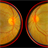

- central retinal artery occlusion (CRAO), retcam, smartphone fundus photography, cherry red spot

- DR.PRITHVI CHANDRAKANTH, ARAVIND EYE HOSPITAL, UDUMALPET

- TRASH TO TREASURE RETCAM

- 37-years-old male with complaints of sudden diminution of vision in the left eye for the past three days. Fundus examination revealed pale retina in the left eye with cherry red spot and normal fundus picture in right eye.